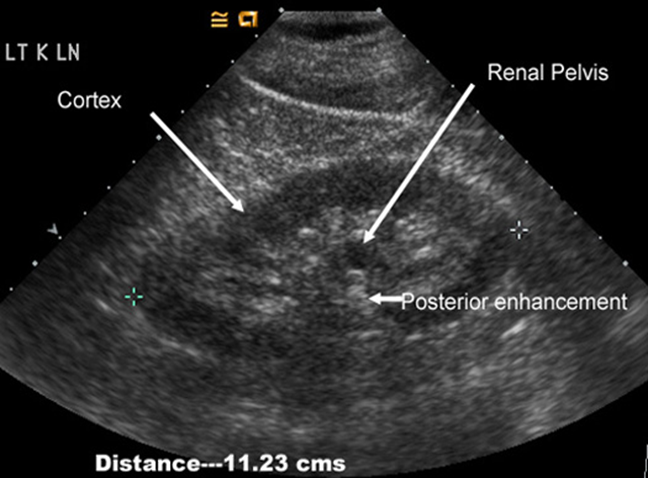

Normal renal ultrasound Z

The kidneys should be smooth in outline. The parenchyma surrounds a central echogenic region, known as the central echo complex (the renal sinus), consisting of the pelvicaliceal system, together with the surrounding fat and renal blood vessels.

The normal pelvicaliceal system is not visible within the renal sinus.

The renal cortex generates homogeneous echoes that are of equal or less reflective than those of the adjacent liver or spleen.

The renal pyramids are seen as triangular hypoechoic areas adjacent to the renal sinus.

The normal adult renal length, measured by ultrasound is 9–12 cm. Renal length varies with age.